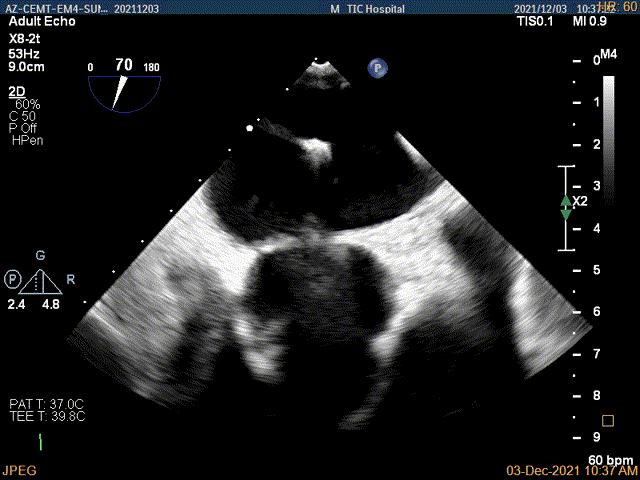

术前超声评估结果

术前超声诊断

3D-color MV view:大量反流,起源于1区

Qlab软件勾画估测瓣口面积约:5.19cm²